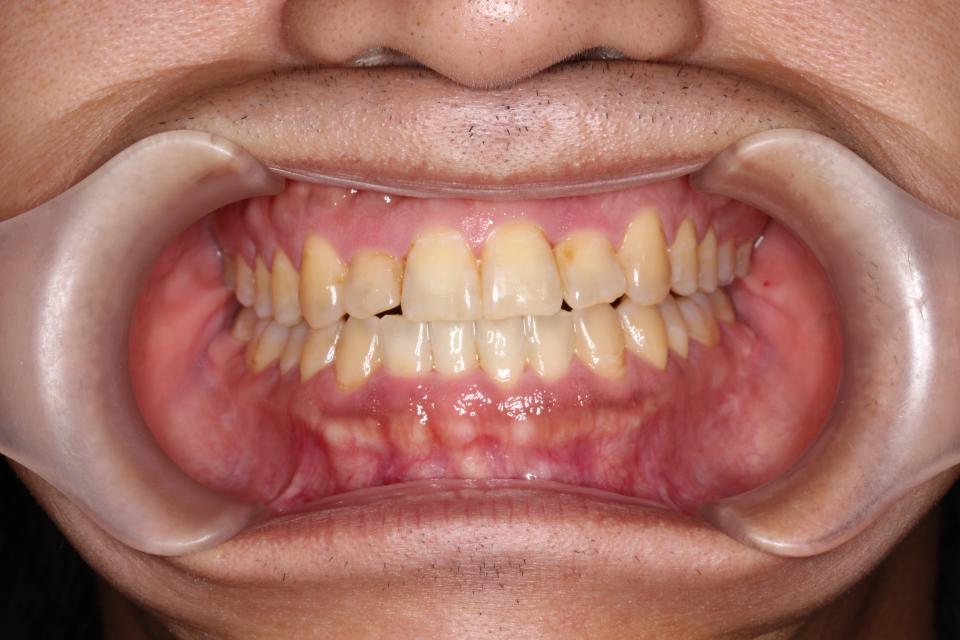

矯正治療後

30代男性です。

| 矯正治療期間 | 2年8か月 |

| 抜歯の有無 | 3本親知らず抜歯 |

| 治療費 | 1005000円 |